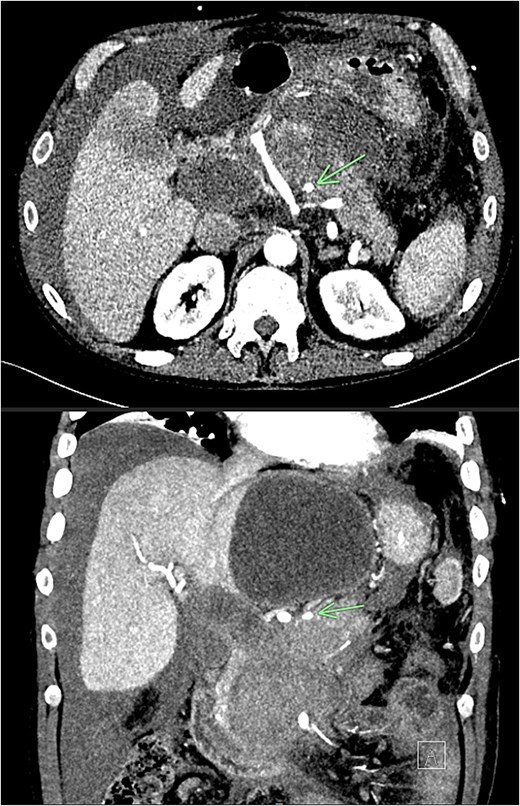

Despite the absence of abdominal symptoms, a computed tomography of the abdomen and pelvis (CTAP) was performed due to markedly elevated lipase levels. The CTAP (Figs 3–5) revealed evidence of acute pancreatitis (Fig. 5, arrow), with a complex peripancreatic fluid collection (Fig. 3, arrow). Additionally, a focal thrombus was observed within the portal venous confluence (Fig. 4, arrow). Further ultrasound of the gallbladder was negative for gallstones (Fig. 6), ruling out gallstone-induced pancreatitis.

Recovery was complicated by progressive necrotising pancreatitis with evidence of active bleeding into a peripancreatic collection (Fig. 7) and a pseudoaneurysm arising from a branch of the superior mesenteric artery (SMA) associated with haemoperitoneum (Fig. 8).

CT angiogram of abdomen axial view; contrast extravasation, indicating active bleeding within this peripancreatic collection.

CT angiogram of abdomen axial and coronal view; small pseudoaneurysm arises from a branch of the SMA (arrow). Large haematoma in the head of the pancreas and diffuse haemoperitoneum throughout the abdomen/pelvis.